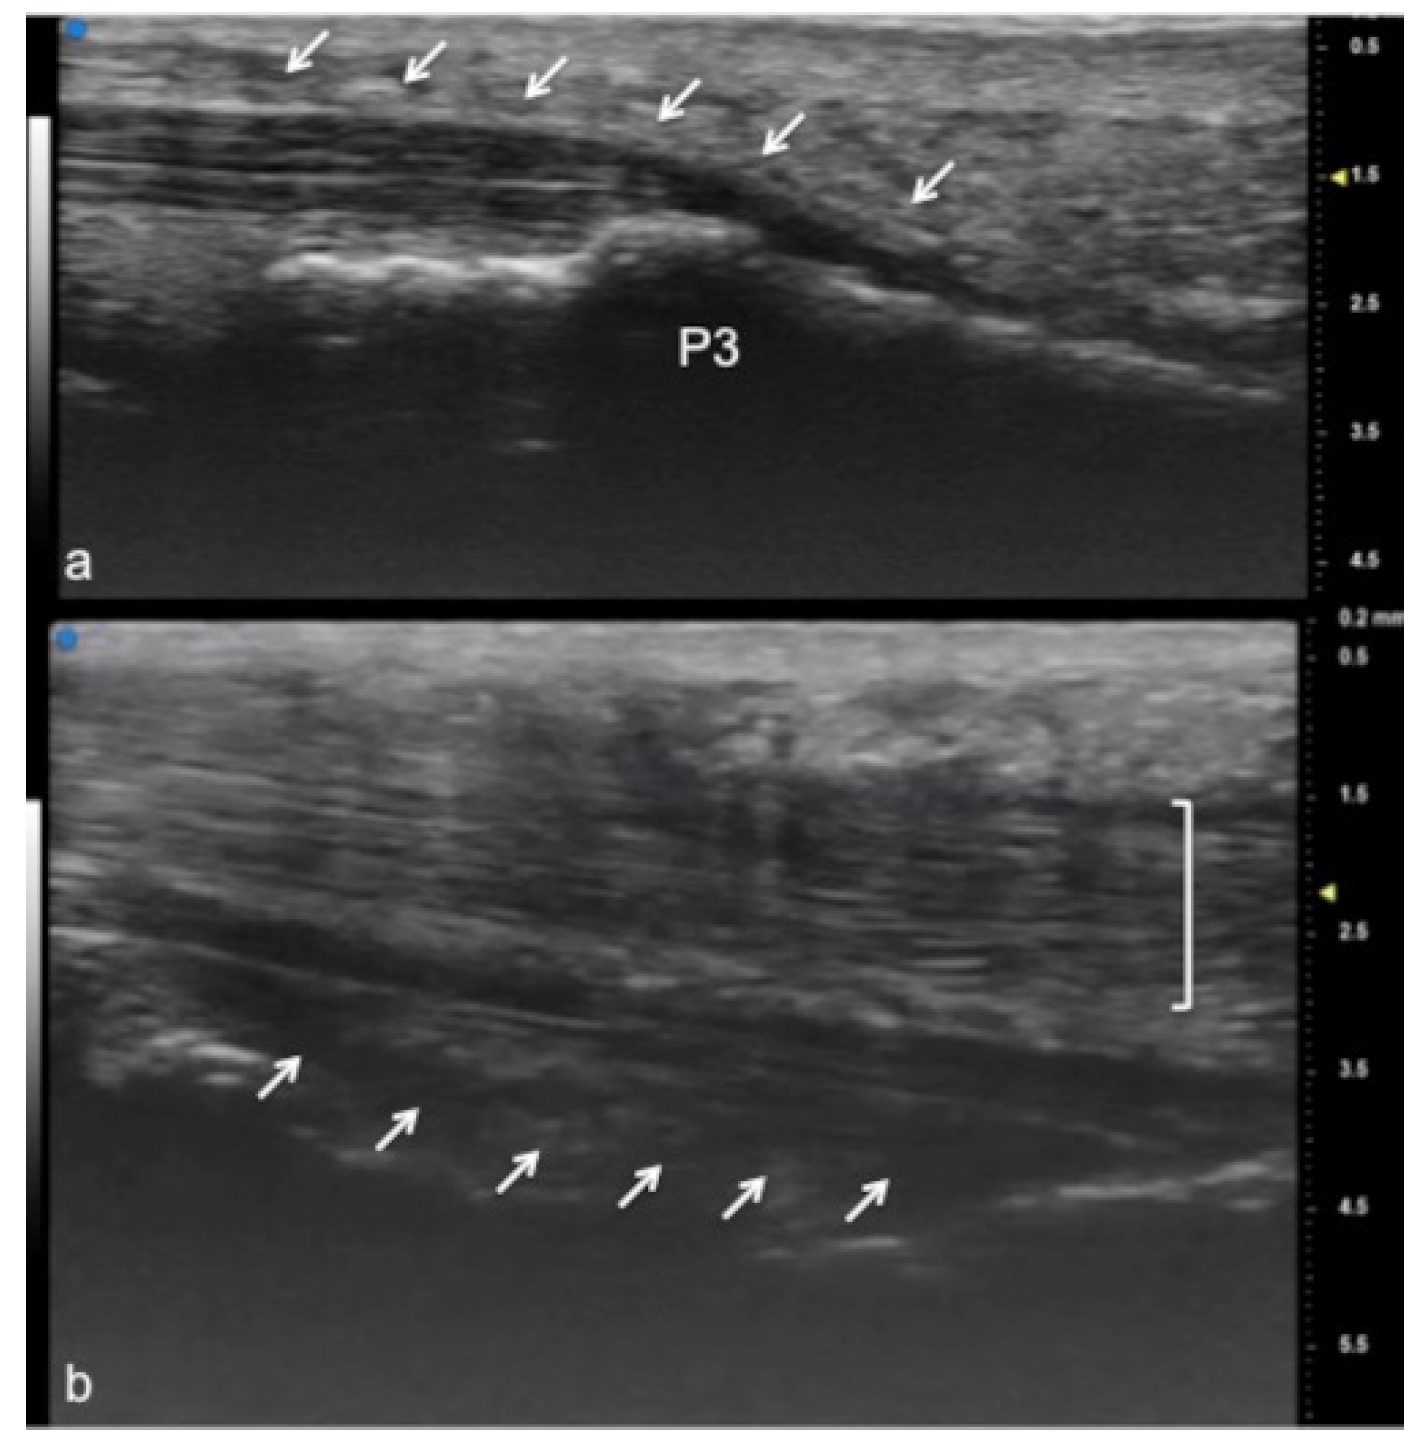

Figure 3.

Flexor tendon of a finger. Using UHFUS at the flexor tendons, the same spatial resolution can be achieved as in the imaging of the extensor tendons. In (a), the sagittal view of the deep flexor tendon component inserting on the basis of the distal phalanx (P3). In (b), the superficial component of the flexor tendon (white arrows) lying near the deep component (white square parenthesis).